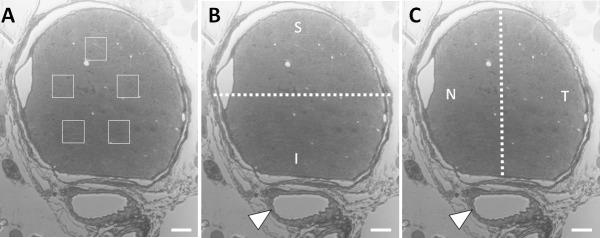

Experimental glaucoma was induced for 6 weeks with a microbead injection model in CD1 (n = 78) and C57BL/6 (B6, n = 68) mice. From epoxy-embedded sections of optic nerve 1 to 2 mm posterior to the globe, total nerve area and regional axon density (axons/1600 μm2) were measured in superior, inferior, nasal, and temporal zones.

Control eyes of CD1 mice have higher axon density and more total RGCs than control B6 mice eyes. There were no significant differences in control regional axon density in all mice or by strain (all P > 0.2, mixed model). Exposure to elevated IOP caused loss of RGC in both strains. In CD1 mice, axon density declined without significant loss of nerve area, while B6 mice had less density loss, but greater decrease in nerve area. Axon density loss in glaucoma eyes was not significantly greater in any region in either mouse strain (both P > 0.2, mixed model). In moderately damaged CD1 glaucoma eyes, and CD1 eyes with the greatest IOP elevation exposure, density loss differed by region (P = 0.05, P = 0.03, mixed model) with the greatest loss in the temporal and superior regions, while in severely injured B6 nerves superior loss was greater than inferior loss (P = 0.01, mixed model, Bonferroni corrected).